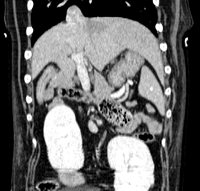

À partir des coupes natives axiales du patient, des logiciels de reconstruction permettent de faire des reformatages dans tous les autres plans (sagital, coronal ou oblique). Enfin, des reconstructions tridimensionnelles peuvent aussi être réalisées avec un rendu volumique, surfacique ou endoscopique.

Abdomen & Pelvis

- Exploration des masses abdominales et pelviennes

- Bilan d'extension abdominal en cancérologie

- Exploration des Shunts porto-systémiques par angioscanner multiphases

- Exploration des organes abdominaux : foie, rate, pancréas, surrénales, reins...